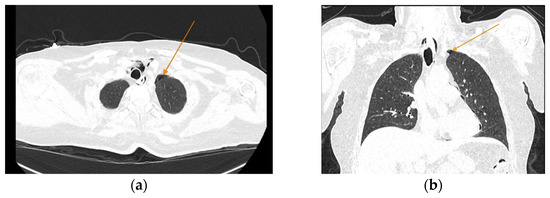

The chest CT scan performed in the emergency department (Figure 1) revealed the presence of pneumomediastinum. CT scans of the abdomen and pelvis were also performed, giving the high lipase and epigastric pain, revealing findings consistent with acute pancreatitis (with peripancreatic fluid collection, consistent with moderate acute pancreatitis per the modified CT severity index), as well as a solitary gallbladder stone measuring approximately 20 mm in diameter, without intra or extrahepatic biliary ducts enlargement (Figure 2).

Figure 1.

Initial chest CT scan, demonstrating pneumomediastinum (arrows): (a) axial view showing free air in the mediastinal space; (b) coronal view revealing air tracking along several mediastinal structures.